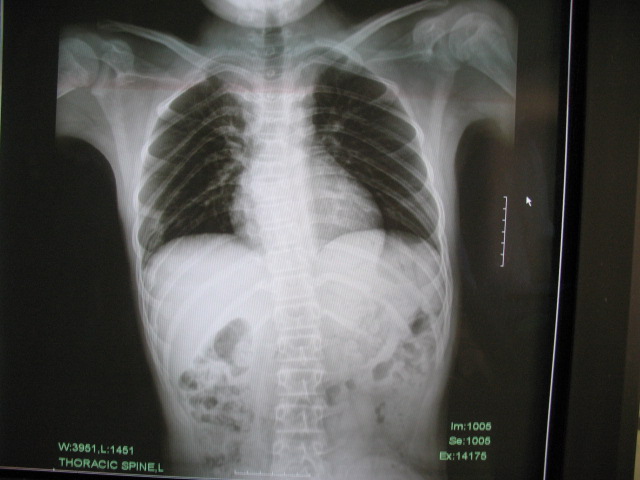

标题: PED0296:男,14岁,身材矮小,全身多处多次骨折 [打印本页]

标题: PED0296:男,14岁,身材矮小,全身多处多次骨折

骨干细而骨端膨大,多发性骨折,临床上可有典型蓝色巩膜、进行性耳聋、脆骨/三联症

成骨不全伴左髋关节脱位。成骨不全是侏儒的病因之一。[url][/url]http://www.radida.com/radinet/read.php?tid=27242

支持成骨不全,细长型

考虑:成骨不全伴左髋关节脱位。